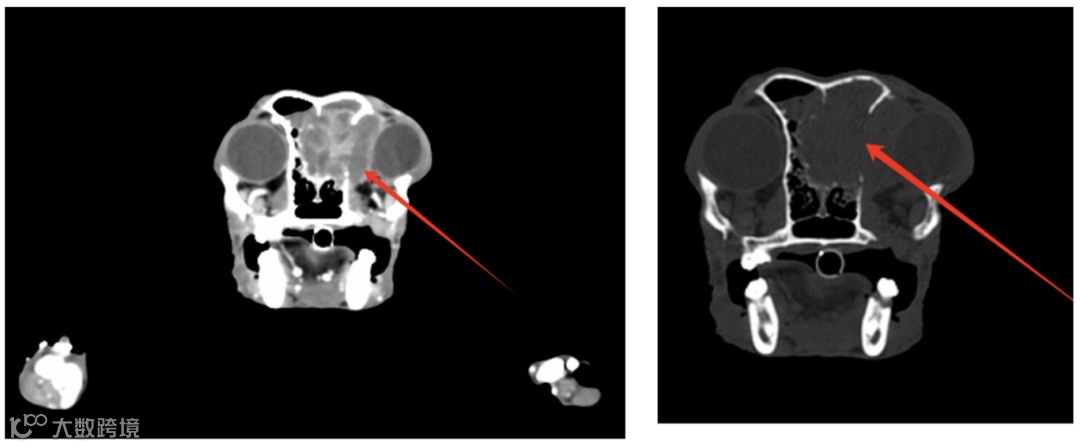

第三、四脑室双侧侧脑室形态扩张

右侧鼻腔及额窦见软组织占位影,增强见不均匀强化,周围骨质见溶骨性改变,你的诊断?